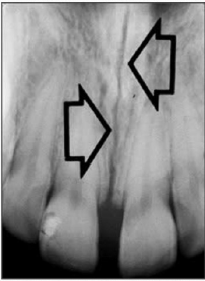

1. What is the anatomical structure indicated by the arrow in this radiograph?